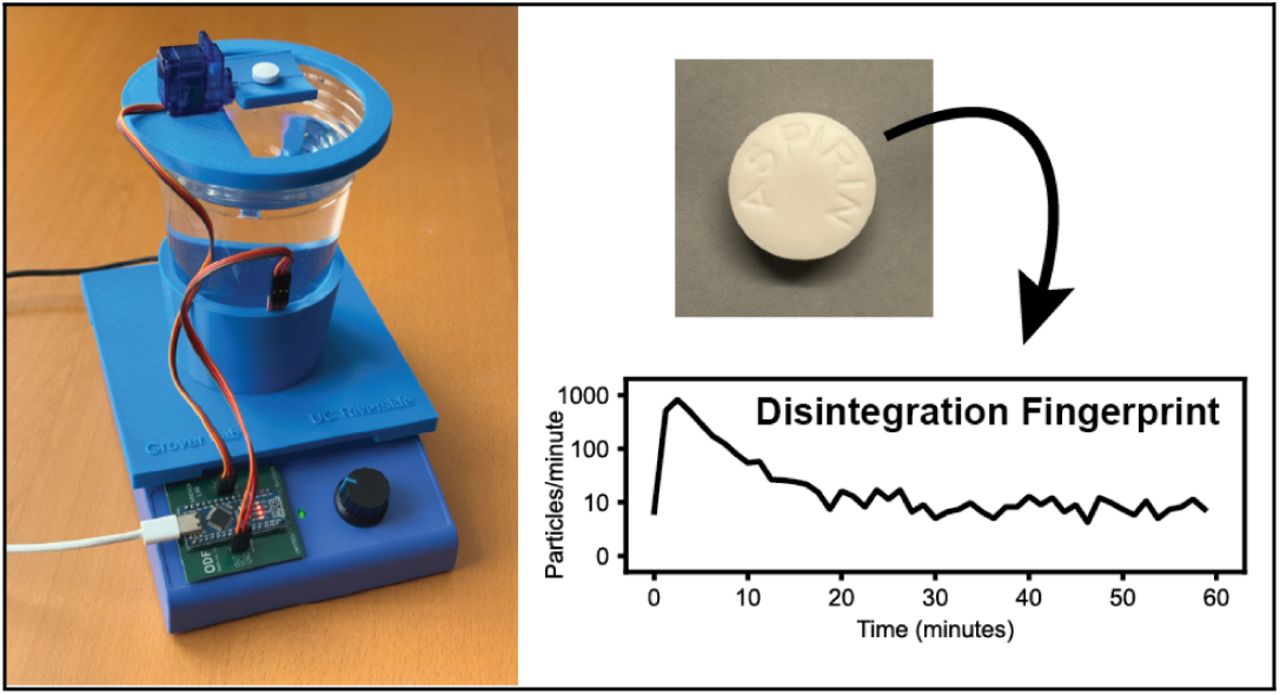

IDing Counterfeit Drugs Might Be Easier Than You Think - ...

Odds are, you’ve taken pills before; it’s a statistical certainty that some of you reading this t...